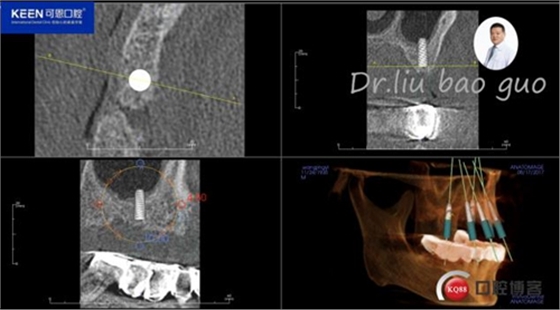

手術(shù)前種植軟件設(shè)計(jì)方案

數(shù)字化種植導(dǎo)板設(shè)計(jì)及制作

手術(shù)過(guò)程

(因設(shè)備限制,未能實(shí)現(xiàn)手術(shù)全程數(shù)字化導(dǎo)板,僅在手術(shù)之前導(dǎo)板定位)